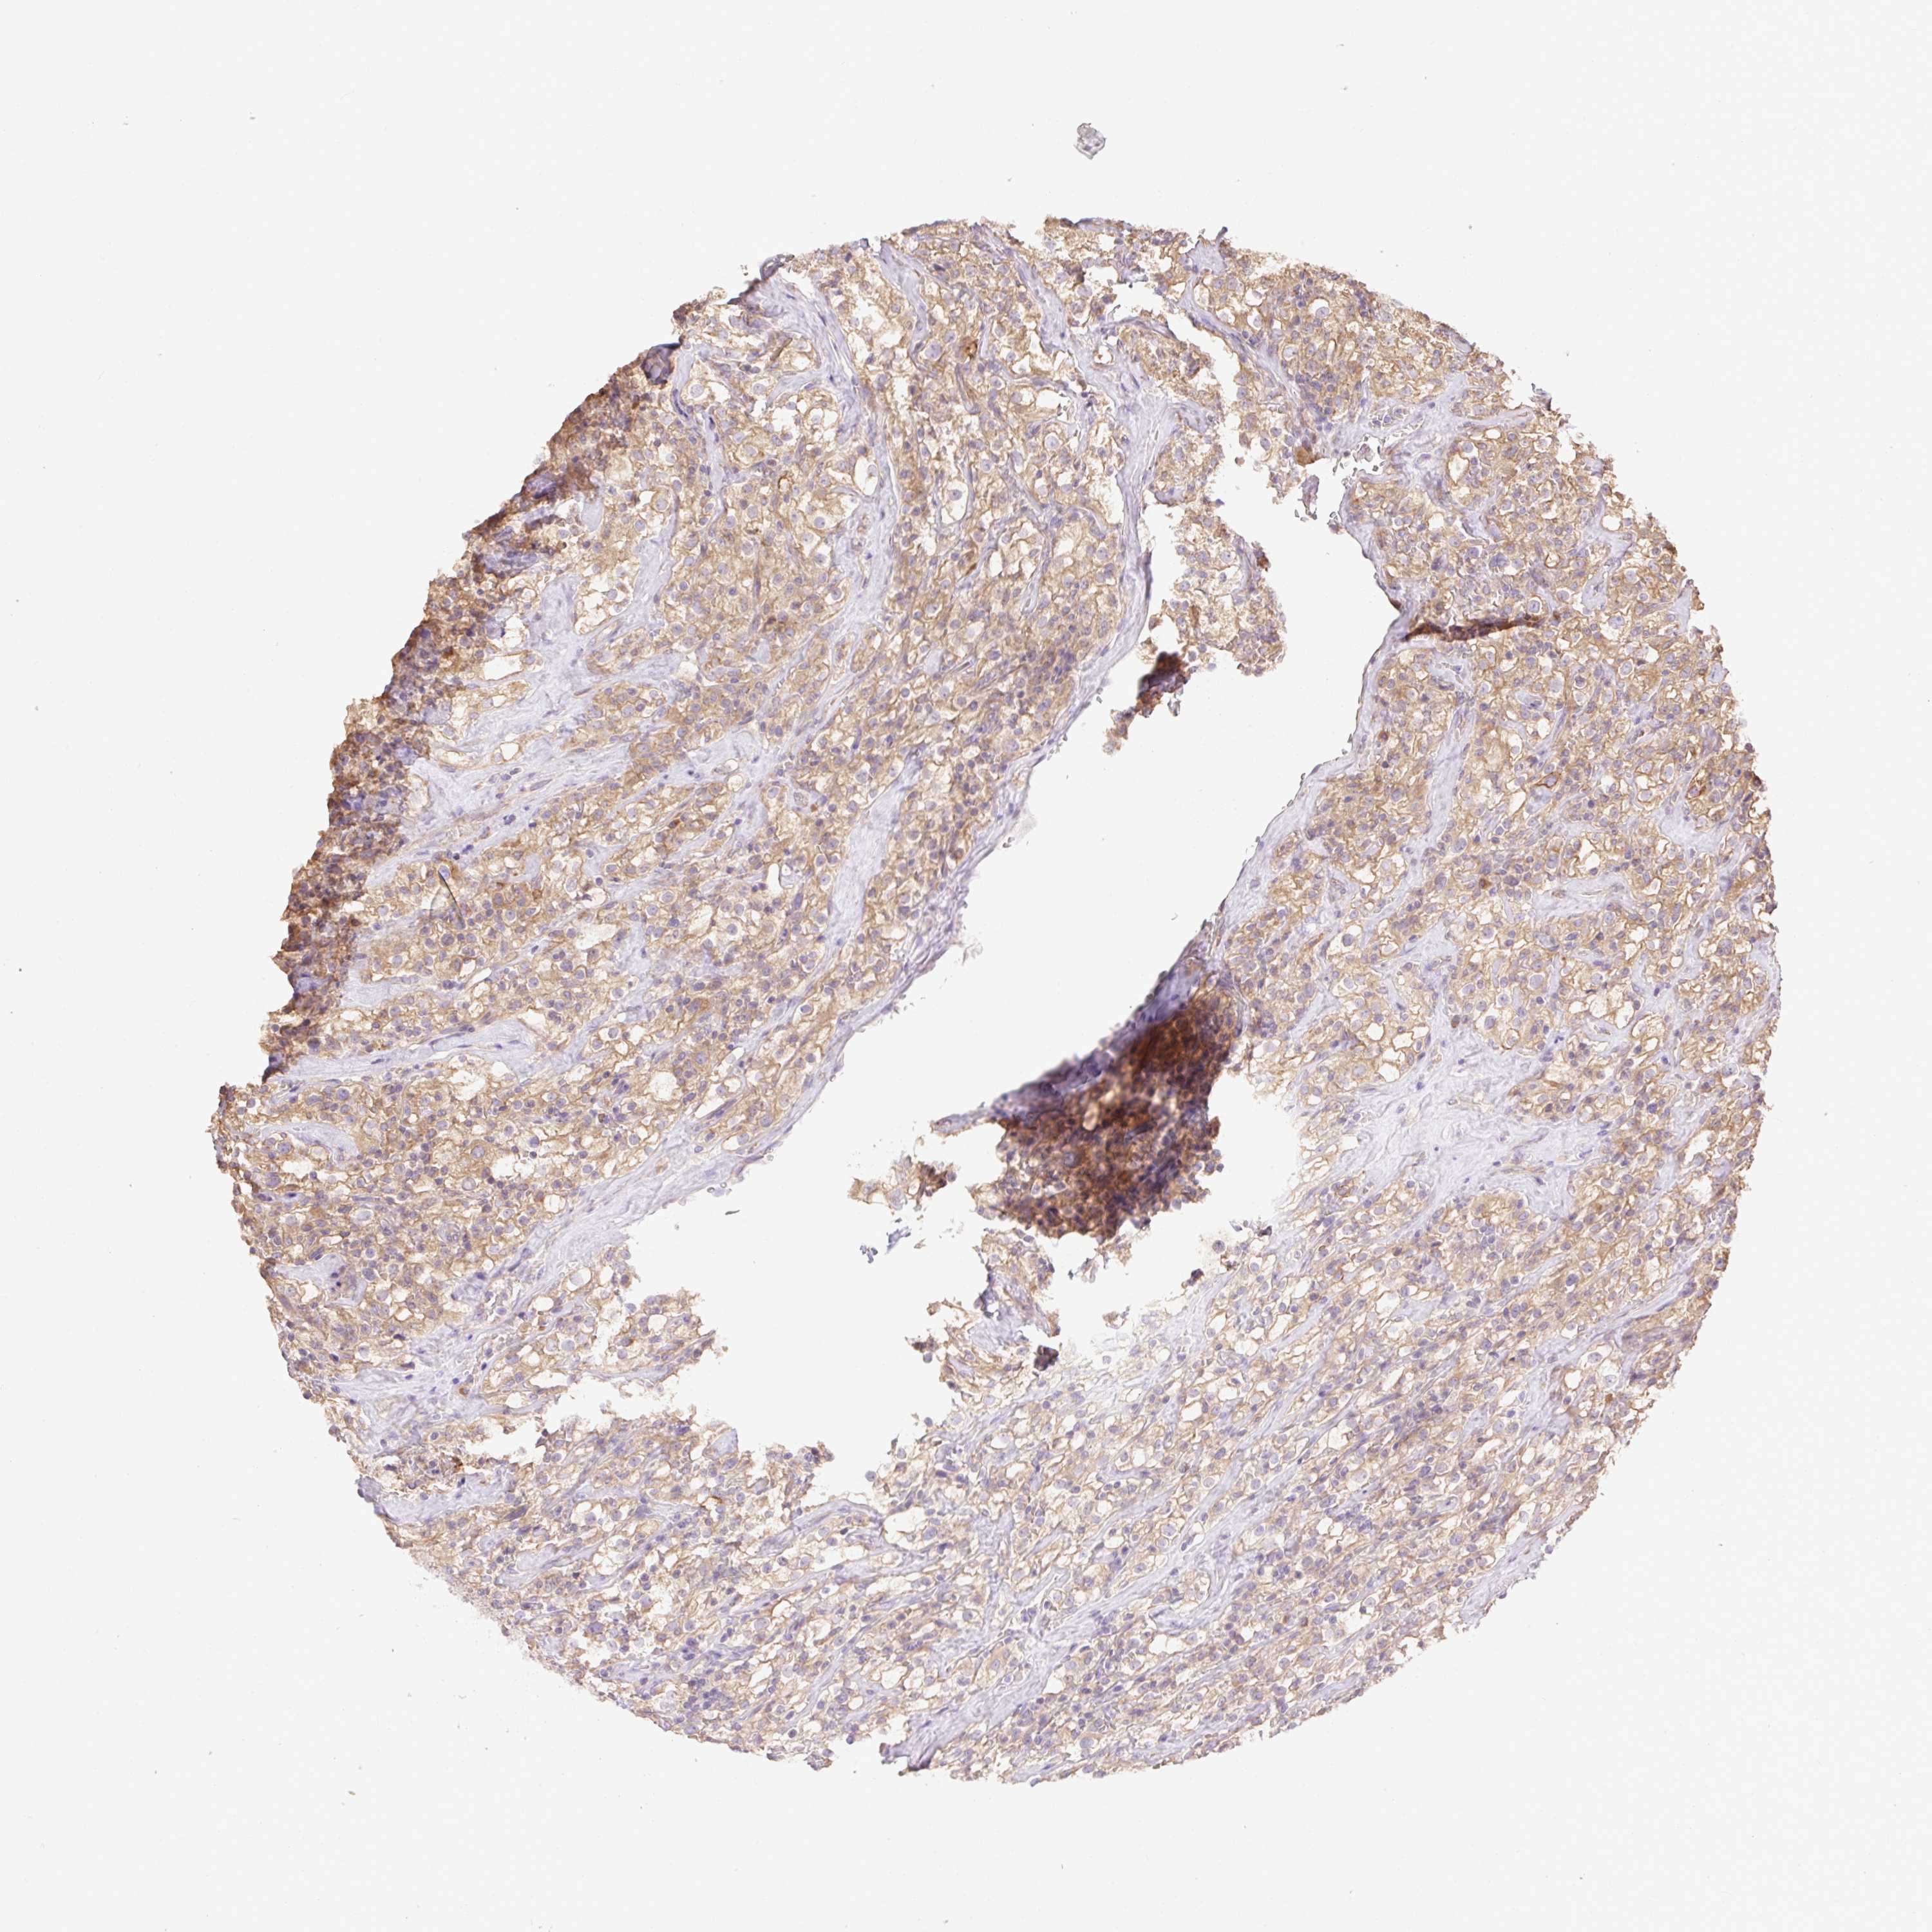

CANCER RENAL CANCER Show tissue menu

KICH TCGA KIRC TCGA KIRC VALIDATION KIRP TCGA PROTEIN RCC CPTAC PROTEIN EXPRESSION